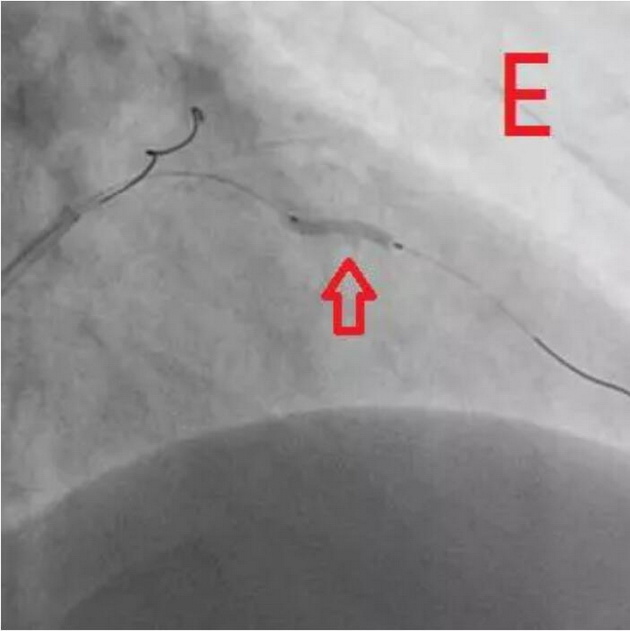

通过对该病变的分析,杨巍主任决定采用“振波球囊”对病变进行预处理。将振波球囊送至环形钙化处并启动4次,随后再次使用预扩球囊对病变处进行扩张,显示可以充分扩张(图E),继续IVUS检查,证实钙化斑块已经裂开(图F)。